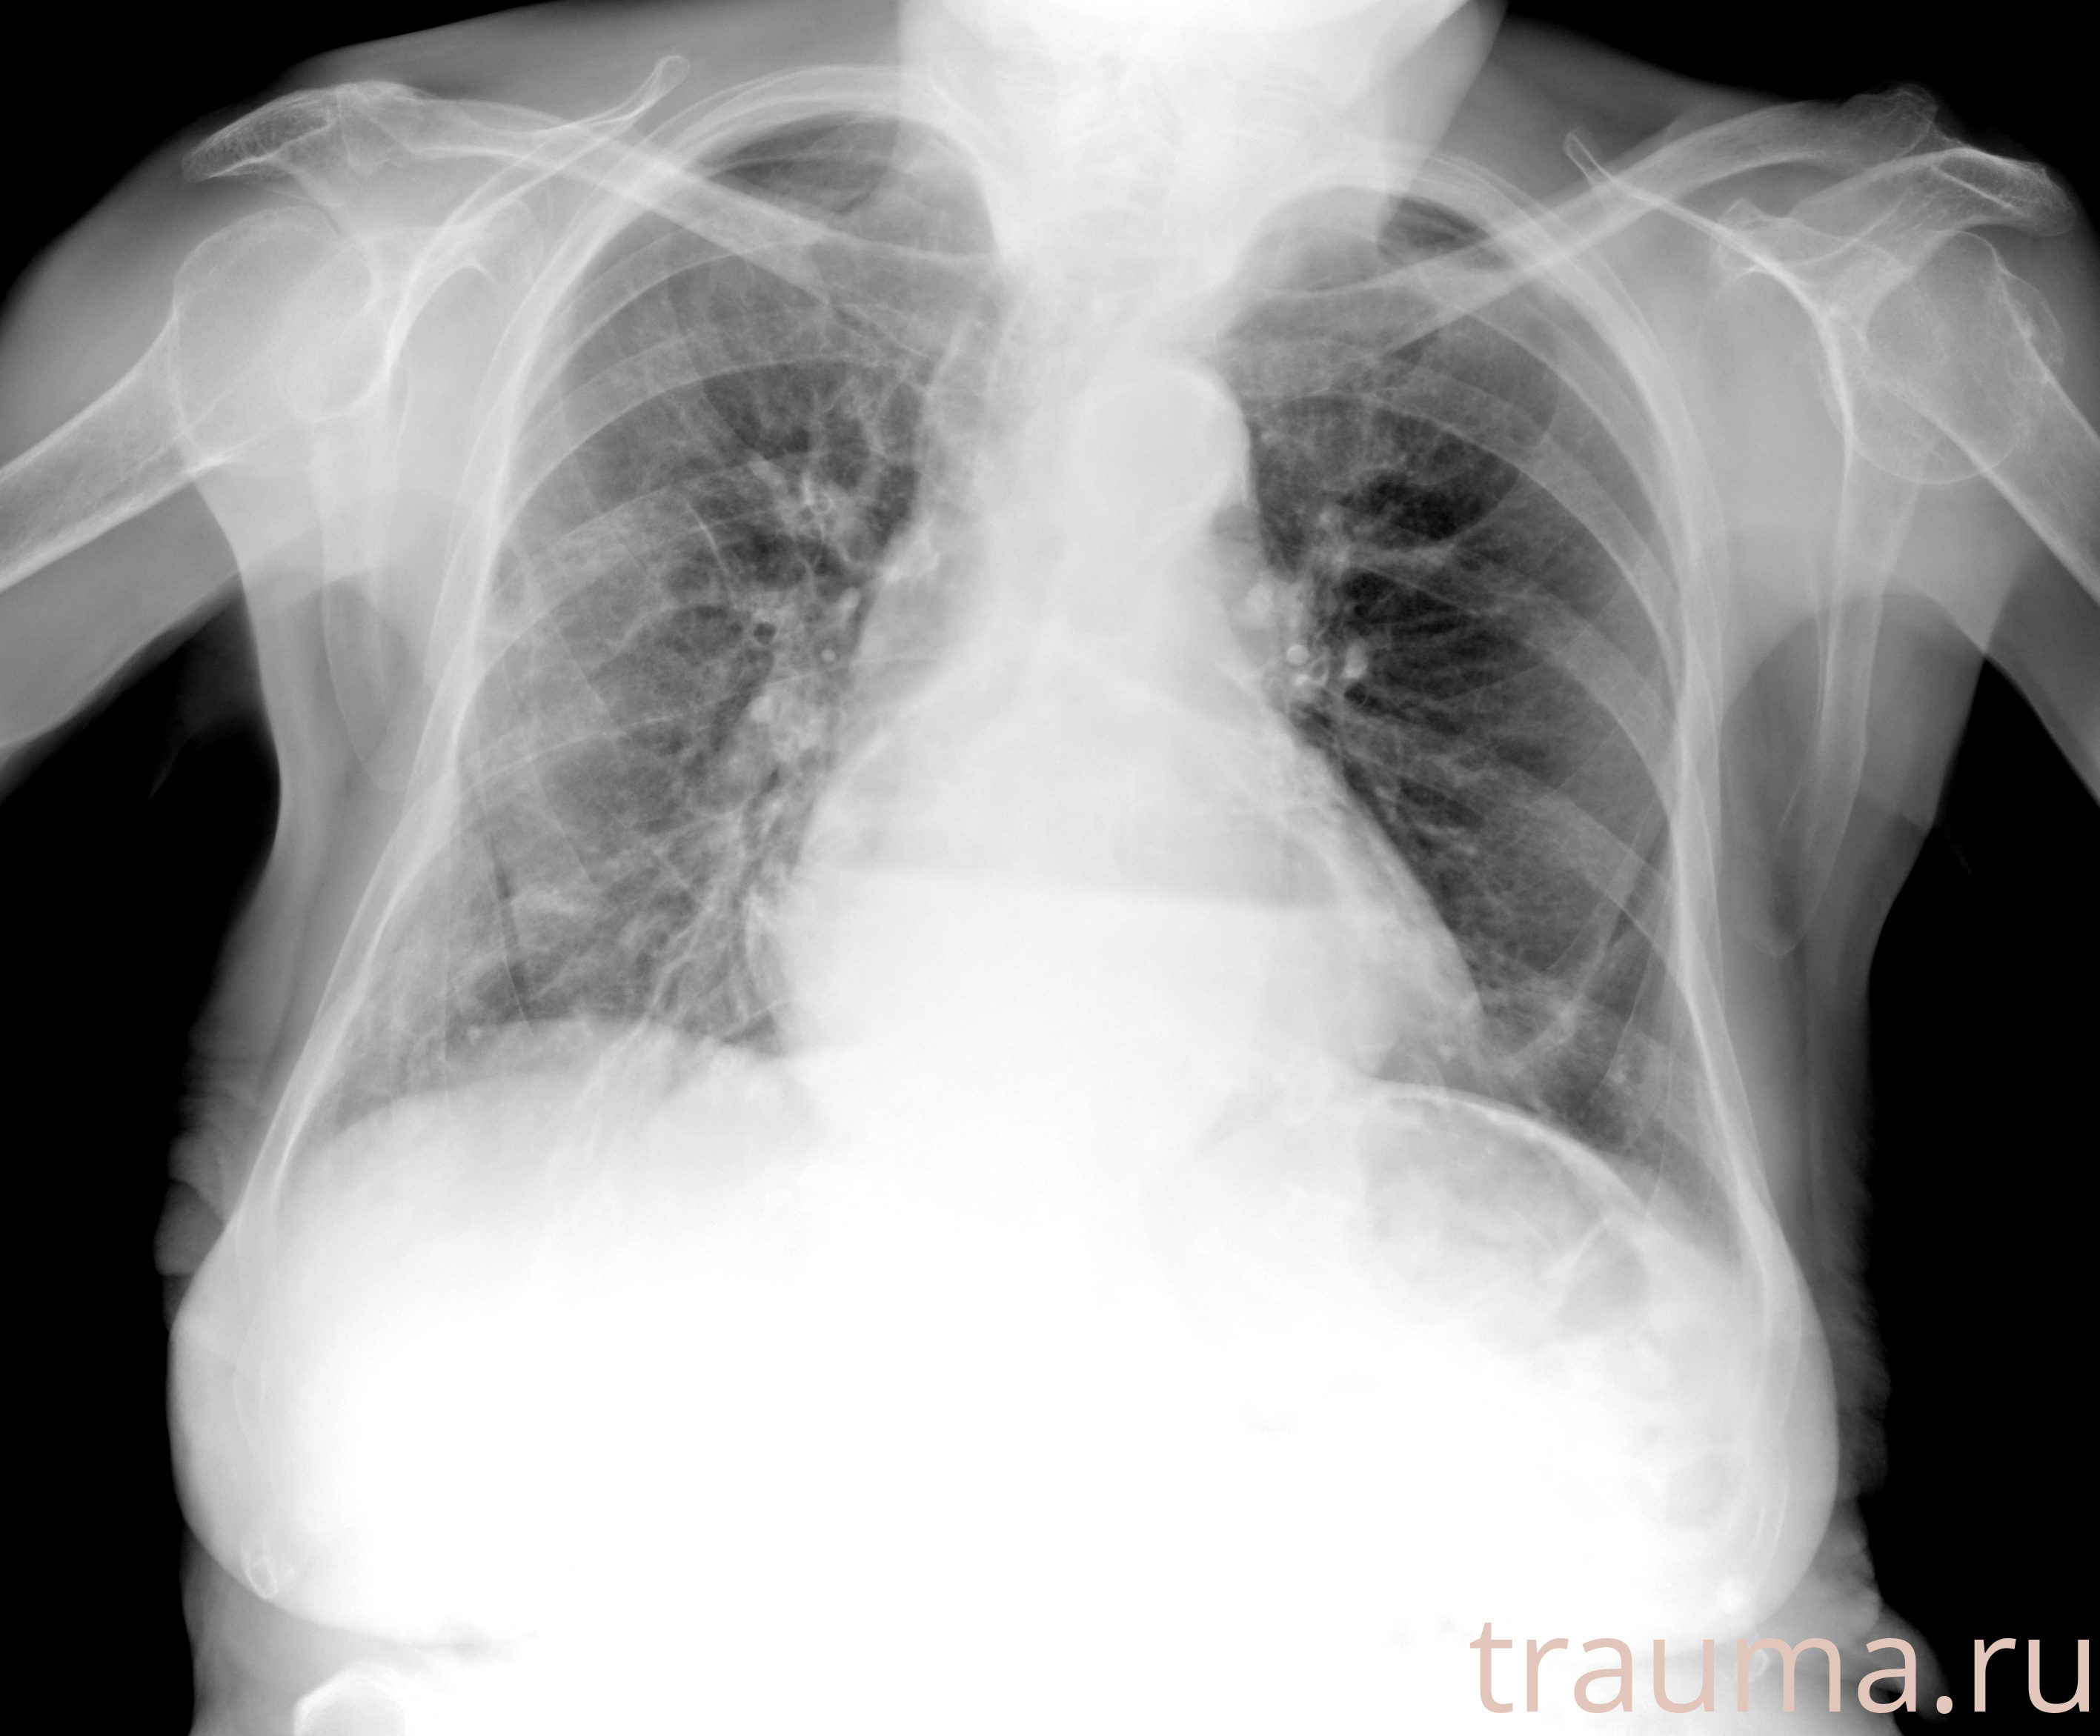

Рентген на дому: по вашему адресу приезжает врач-рентгенолог, травматолог-ортопед с мобильным рентгеновским аппаратом, проводит диагностику травмы или заболевания, делает необходимые рентгенограммы, дает рекомендации по дальнейшему лечению. Получить качественные снимки в домашних условиях возможно благодаря уникальной методике, разработанной МосРентген Центром для института  Склифосовского